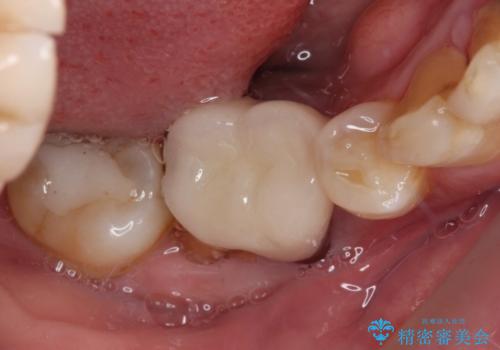

外れてしまった奥の銀歯 オールセラミッククラウンによる補綴治療